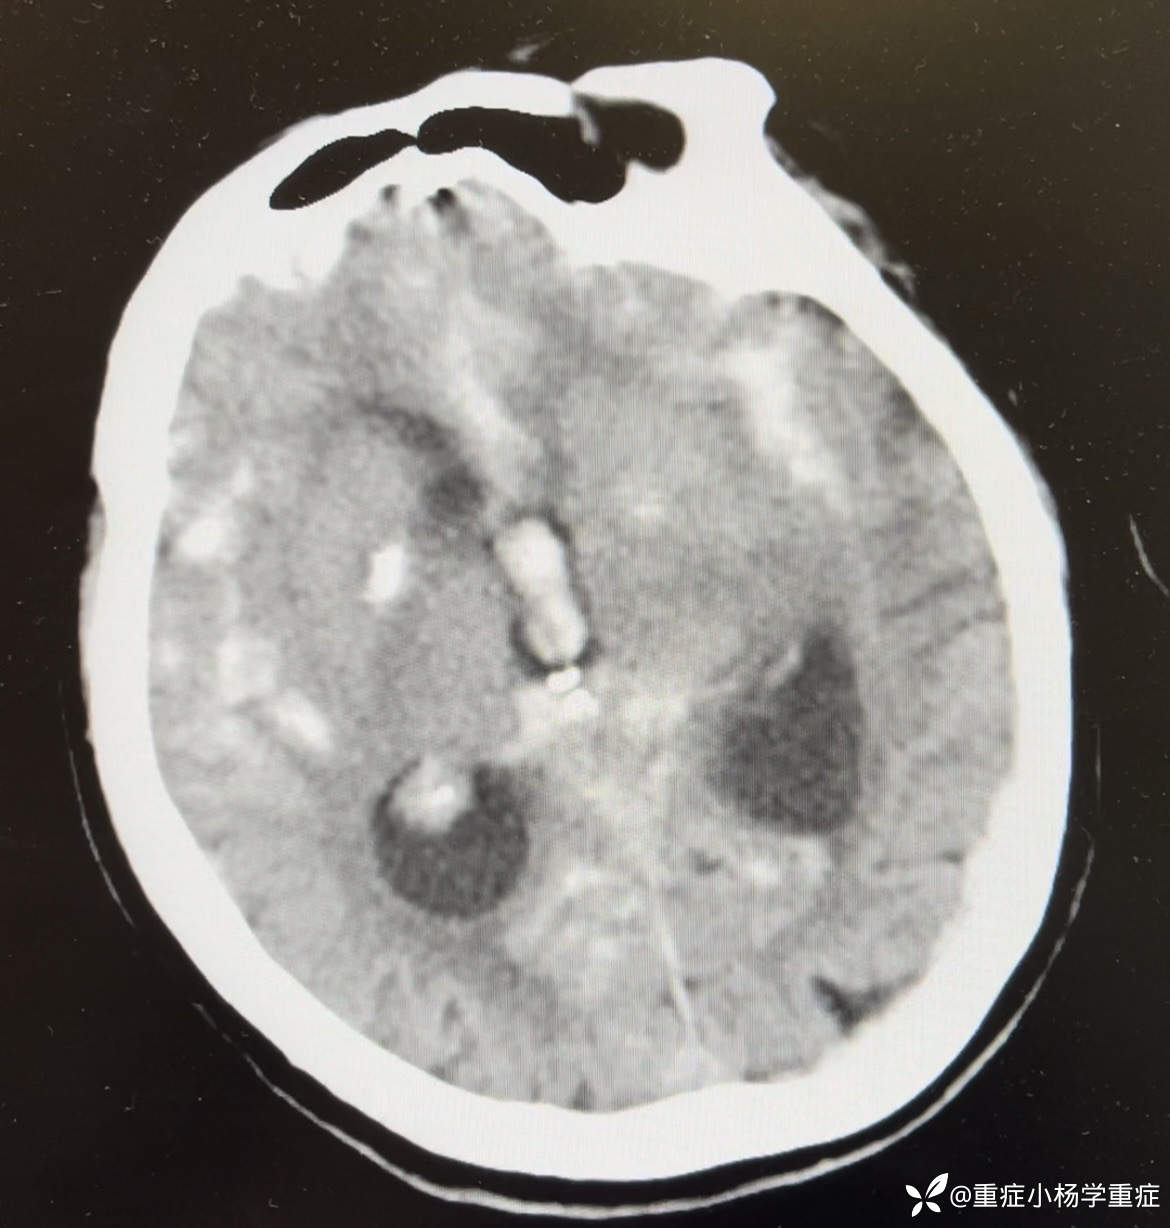

简要病史:患者于7小时余前吃中饭时突发意识不清,头撞到桌面,呼之不应,无抽搐,家属拨打120送我院急诊,测脉搏105次/分,呼吸14次/分,血压:207/92mmHg,SPO2 95%,至急诊后出现呕吐2次,为胃内容物,行CT检查提示:蛛网膜下腔出血破入脑室系统;予以氨甲环酸止血、尼莫地平防止脑血管痉挛、乌拉地尔控制血压,请神经外科会诊考虑“动脉瘤破裂出血”建议行CTA明确诊断及手术治疗,患者家属经商讨后拒绝CTA检查及手术治疗,要求行保守治疗,经我科会诊后以“蛛网膜下出血、脑血管意外、高血压”收住院治疗。

辅助检查:生化:肌酐128.9umol/L↑,钠146.3mmol/L↑。CT平扫:1.蛛网膜下腔出血破入脑室系统;2.老年脑改变;3.考虑两肺少许炎症,随诊复查。